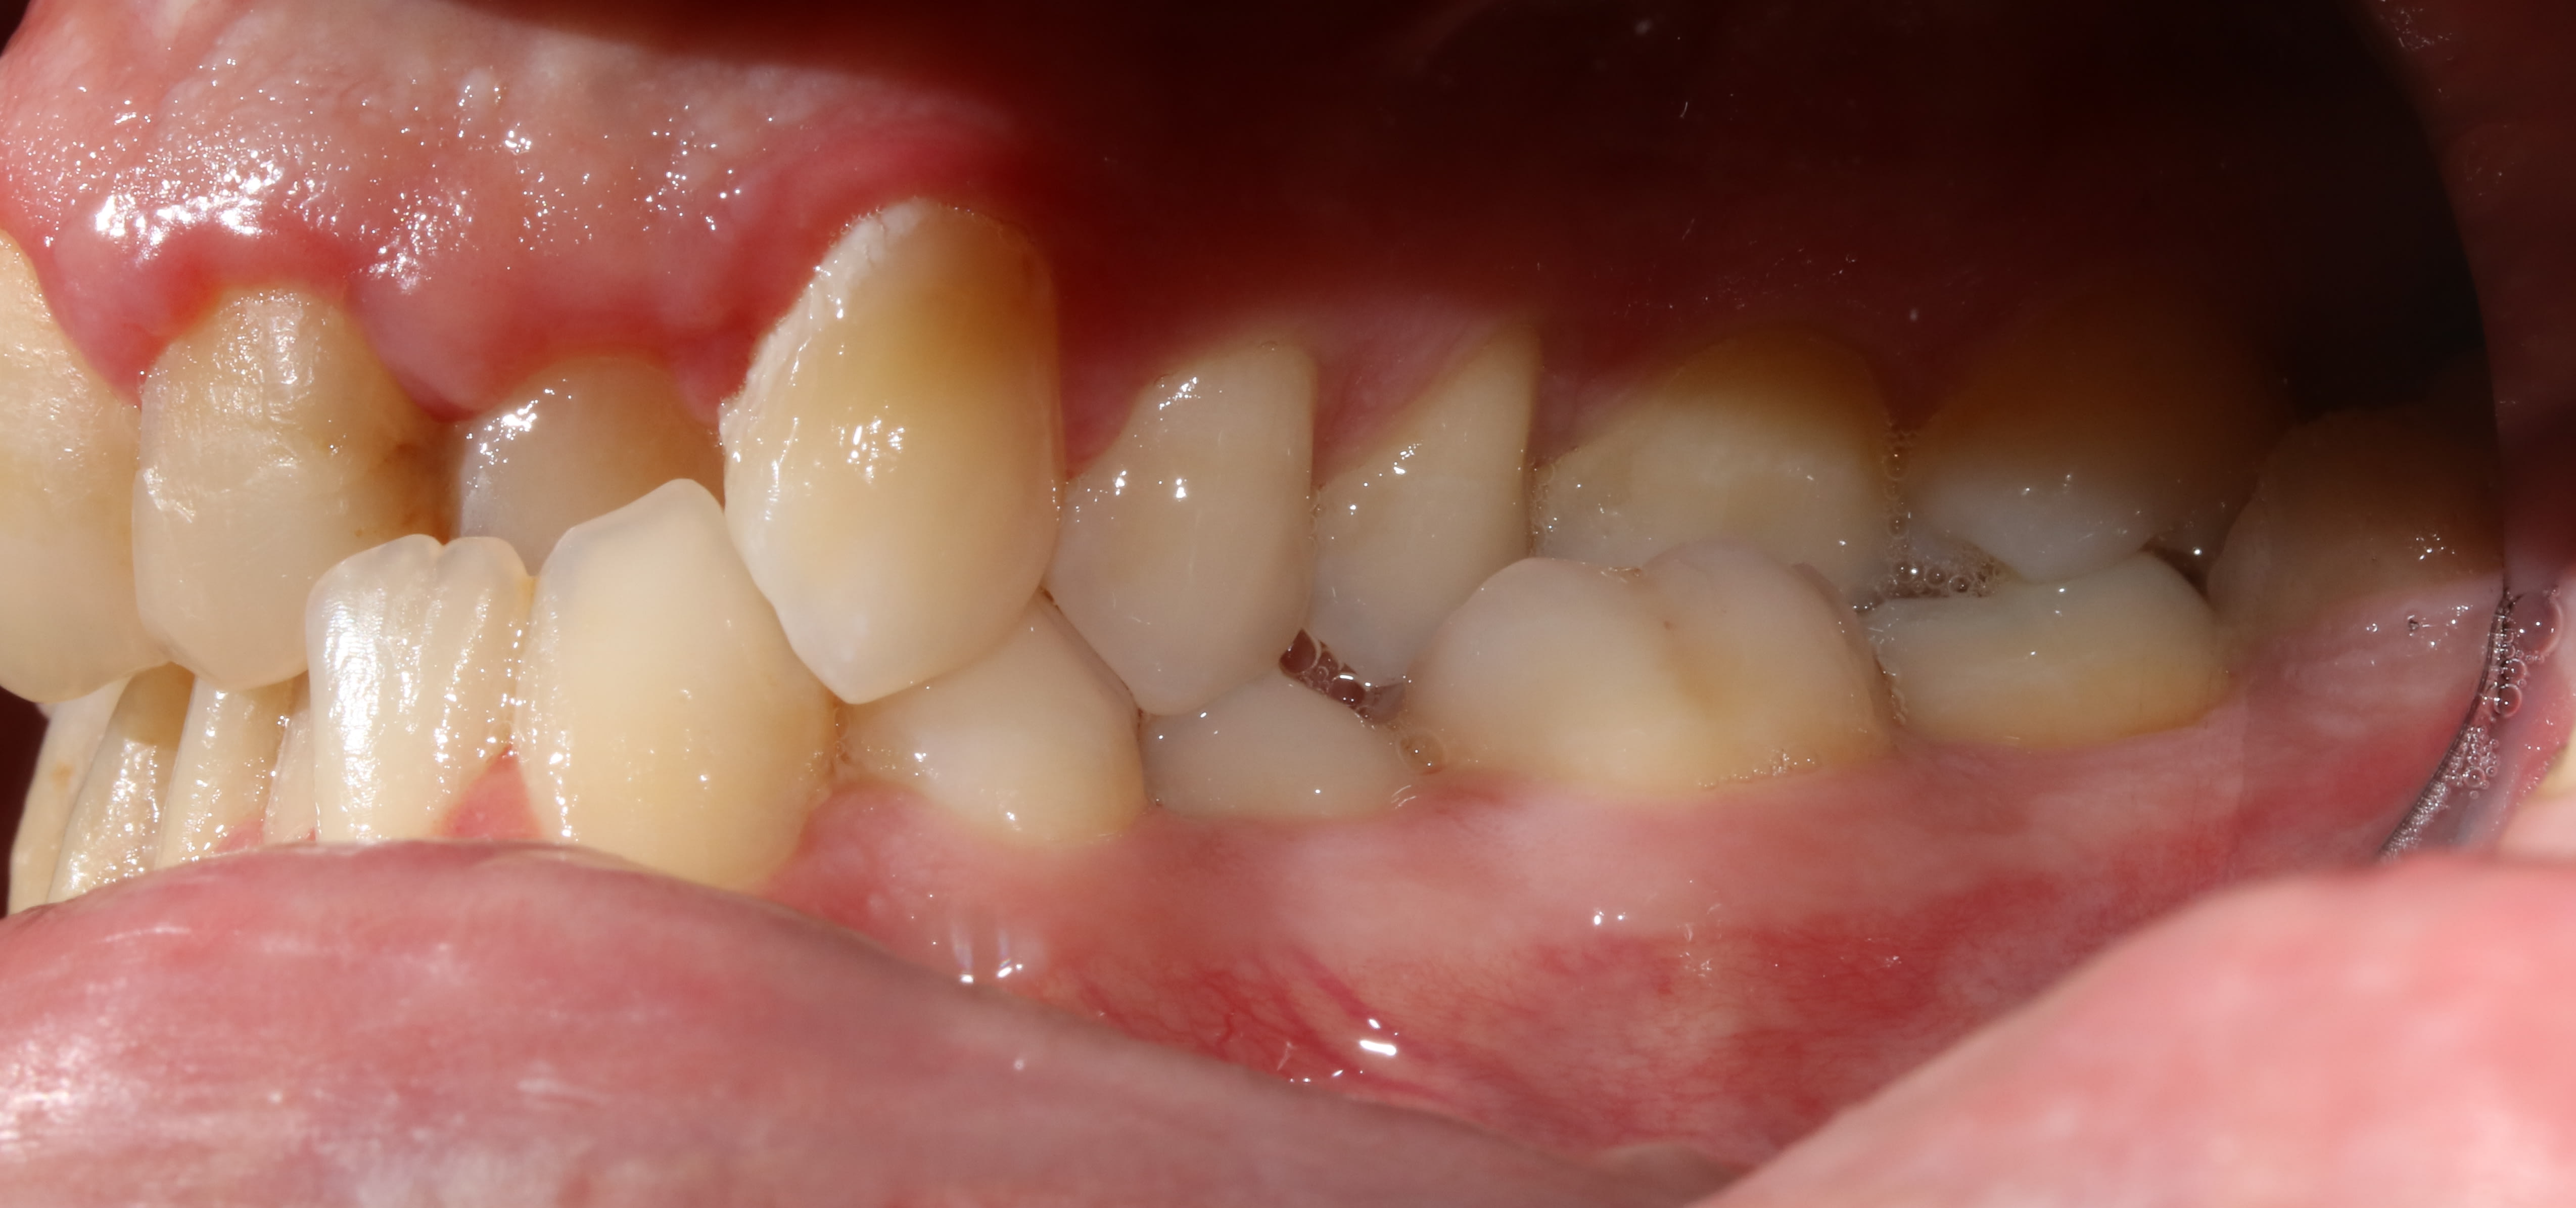

Patient quarante cinq ans. Bruxe, serre, tendu acouphénes, cephallées, visites recurrentes chez les osteo sans resultats, cadre sup ingenieur boite helicos bien connue, stressé++++, vit à 200 à l'heure....

Ici pas possibilté remonter la dv car en quasi bout à bout de base.

Dents naturelles m'interdisant d'envisager de la prothèse en premiere intention.

Faire une gouttiere l'aurait peut être amené à un positionnement plus confortable mais aurait conduit à reconstruire ensuite les dents pour se caler comme avec la gouttiere.

Solution qui aurait certes été lucrative mais allait à l'encontre de mes principes et de son portefeuille (quoi que, chez airbus, les cadres (pas les os, faut pas deconner) y z'ont une bonne mutuelle..... ais-je été con?).

Du coup lui ai refilé un activateur de soulet et besombes et expliqué quoi en faire. Au passage, certains appellent ça "dentosophie" et disent que ça marche jamais!

L'a porté consciencieusement, en a bouffé beaucoup mais on a obtenu "ça" en moins d'un an.

Mieux du point de vue DDM et inversé de l'articulé, mieux en "général" aussi même si je l'ai envoyé faire de l'hypnose pour finir de gérer le stress ... Chez un pote à halboy